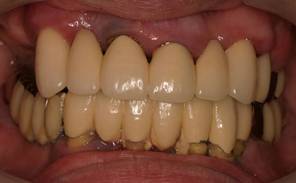

術前。62歳男性。仮の歯の入っている上顎前歯部は抜歯するしかない状態。右下がない為右上臼歯が伸びだしていました。入れ歯では咬めないのでインプラントを希望され紹介されて来院されました。

63歳術後。よく噛めるようになり喜んでいただけました。